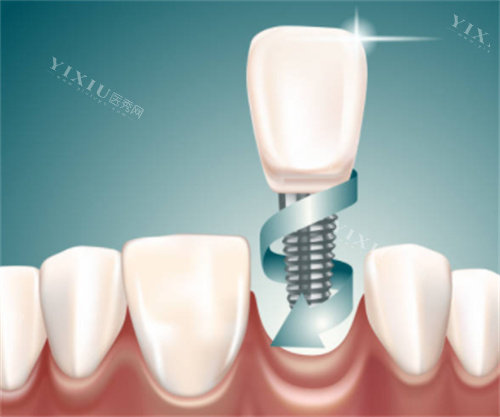

在牙齿缺失修复领域,种植牙成为了众多患者的首要选择。韩国维钛种植体和奥齿泰种植体作为市场上备受关注的两大品牌,很多人在选择时都会犯难:到底哪个更好呢?接下来,我们就从多个方面对这两种种植体进行详细对比,帮你做出明智的选择。

材质与表面处理技术

奥齿泰:四级钛合金与纳米技术

奥齿泰种植体通常采用四级钛合金材料,表面采用多孔纳米氧化钛技术处理,结合 SA 喷砂酸蚀处理,增加了种植体的生物活性,减小了术后的排异性,提高了种植体的存活率。这种材质的特性使其在与骨组织结合方面表现出色,特别适合直径大于 4mm 的种植体。

维钛:四级冷作钛与 SLA 技术

维钛种植体采用四级冷作钛材质,这种材质纯度高(高达 99% 以上),具有良好的生物相容性,能显著减少排异反应,促进骨组织的愈合与融合。同时,其耐磨性和耐腐蚀性也更强,适合长期口腔使用。表面采用 SLA 喷砂酸蚀技术,能让骨头细胞更快 “爬” 上去生长,将传统 3 - 6 个月的愈合期缩短至 1 - 2 个月。

奥齿泰种植体采用了喷砂加酸蚀(SA)表面处理工艺,能够增加螺纹表面的粗糙度,从而提高种植体的初期稳定性。此外,根端设计为 3 刃螺旋切割的形状,使得其具备较好的自攻性,缩短了骨愈合的时间,通常在 4 到 6 周就可以负重。其 GS/TS、SS、US、MS 等多个系列,每个系列都有独特的优势,能适应各种复杂的口腔环境。

维钛种植体的锥形结构模仿天然牙根,尤其适合牙槽骨条件差(如骨头凹陷)的患者,能减少手术中对邻牙和神经的损伤,操作时间比传统种植体快 30%。同时,其拥有差异化清洁系统,如独特的 8 槽真空超声波清洗系统,能够有效去除种植体表面的杂质和化学物质,确保患者的口腔健康。